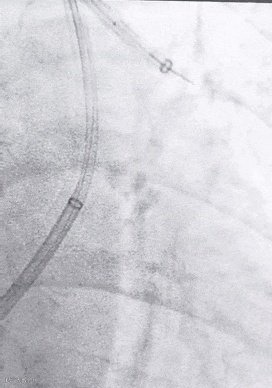

SWAM技术在下肢DVT中的应用:

8F天航抽吸导管与7mm天戟分离器完美配合,高效清除血栓。

导管+分离器,抽拉结合